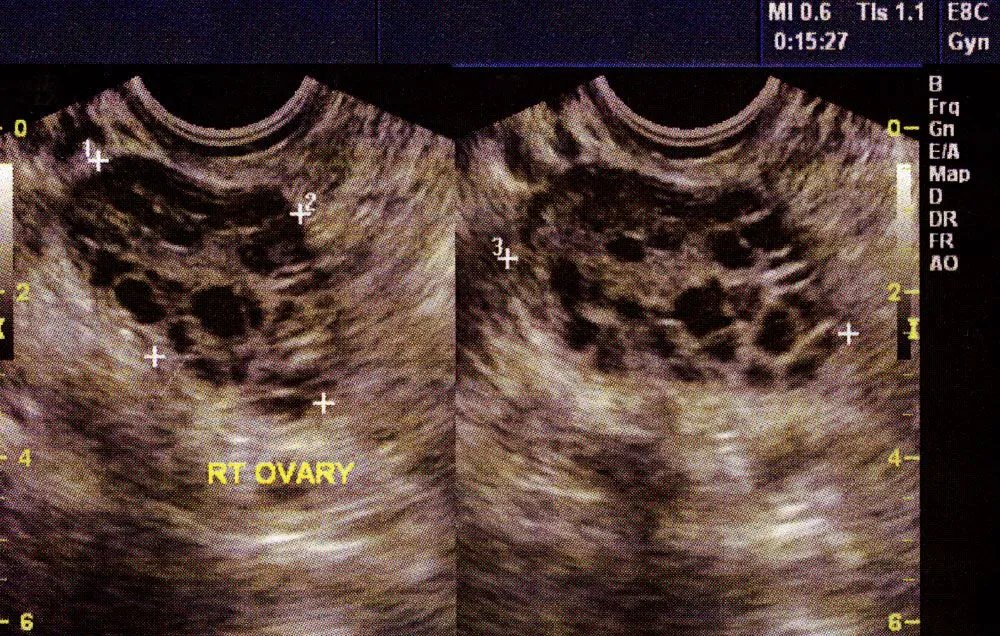

PCOS.

One common cause of PCOS actually stems from the gut believe it or not.

Let’s talk about the link between a bad gut and PCOS: Image Hyperandrogenic PCOS is a common hormonal disorder that affects a TON of women.

(Not medical advice) Image